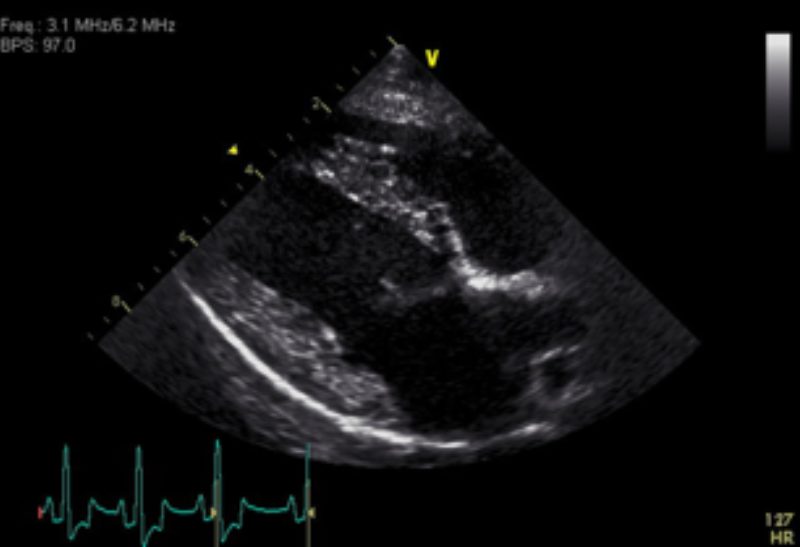

Die Besitzerin berichtete, dass „Timmi“ beim Einladen in das Auto kurz zusammengebrochen sei und sich sein Zustand bei der Anfahrt noch weiter verschlechtert hätte. In der Untersuchung war der Hund sehr matt und atmete verstärkt (Bild 1). Neben blassen Schleimhäuten und einem schwachen Puls war vor allem eine deutlich erhöhte Herzfrequenz bei eher leisen Herztönen auffällig. Eine Röntgenaufnahme des Brustkorbes zeigte eine deutlich vergrößerte und abgerundete Herzsilhouette und führte zu dem Verdacht eines Herzbeutelergusses (Bild 2). Zur weiteren Abklärung wurde ein Herzultraschall durchgeführt, womit die Verdachtsdiagnose schnell bestätigt werden konnte (Bild 3).

Aufgrund der lebensbedrohlichen Situation ist umgehendes Handeln erforderlich. „Timmi“ erhielt zunächst zur Stabilisierung des Kreislaufes Flüssigkeit über einen Venenzugang. Anschließend wurde der Bereich der Punktionsstelle rasiert, desinfiziert und örtlich betäubt. Die Flüssigkeit im Herzbeutel wurde mit einer Kanüle, die über einen Schlauch mit einer großen Spritze verbunden ist, abgezogen. Bei „Timmi“ ließen sich 310 ml rötliche Flüssigkeit entfernen (Bild 4). Nach der Punktion konnte man im Ultraschall bereits erkennen, dass das Herz - insbesondere jedoch der rechte Vorhof - wieder gut gefüllt war und sich besser kontrahierte (Bild 5). Die Laboruntersuchung des Flüssigkeitspunktats ergab ein blutiges Zellbild. „Timmi“ war direkt nach Abpunktion der Flüssigkeit wieder deutlich agiler und nahm bereits Futter auf. In Absprache mit den Besitzern entschieden wir uns, ihn für weitere Untersuchungen und zur Kontrolle der Ergussmenge am Folgetag für eine Nacht stationär aufzunehmen.